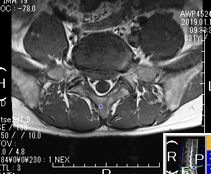

椎間板ヘルニア

2年前から腰痛を感じ少しずつ悪化、1年前に整形外科を受診し、MRI検査で椎間板ヘルニアと診断される。